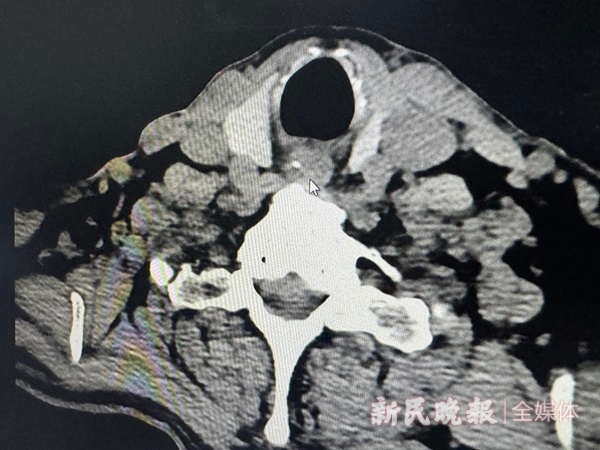

图说:CT报告上箭头所指的就是一根鱼刺

“一般能看到的就能取出,这个鱼刺看不到,就要做个CT。”王医生说,在CT报告上,能清晰地看到这根鱼刺卡在了食管,耳鼻喉科医生已无法在急诊室施展“技能”。她建议徐先生晚上不要再吃喝东西,急诊入院全麻下硬管食道镜下取或第二天一早去综合性医院做胃镜取出。